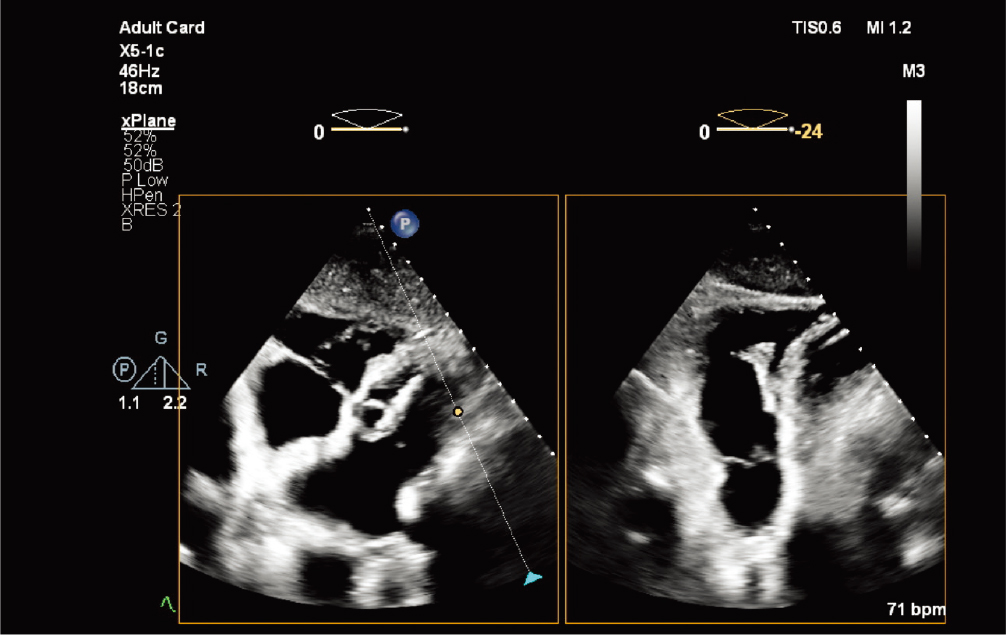

X5-1c探头

X5-1c 探头配备 nSight Plus,有助于优化 TTE 成像 |

X5-1c 探头肋下 xPlane 肺动脉图像 |